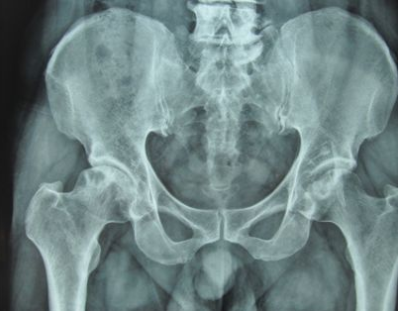

郑州股骨头坏死医院:药酒可以治疗股骨头坏死吗?

郑州股骨头坏死医院介绍股骨头坏死在临床当中是一种常见病,也是多发病,形成的原因有很多…[详情]

河南治疗骨科医院:股骨头坏死如何进行功能锻炼?

河南治疗骨科医院介绍当我们已经明确存在股骨头坏死时,而且我们了解我们股骨头坏死的程度…[详情]

郑州治疗股骨头坏死医院:股骨头坏死病因有哪些?

郑州治疗股骨头坏死医院介绍股骨头坏死这种疾病可以说是一种比较严重的疾病,这种疾病发生…[详情]

河南股骨头坏死专科医院讲解中医股骨头坏死怎么治疗

河南股骨头坏死专科医院介绍股骨头坏死是骨科特别常见的一种疾病,也是一种多发病。股骨头…[详情]

股骨头坏死都有哪些症状?郑州治疗骨科医院为您讲解

郑州治疗骨科医院介绍股骨头坏死是临床上特别常见的一种疾病,而且这种疾病可以说是特别严…[详情]